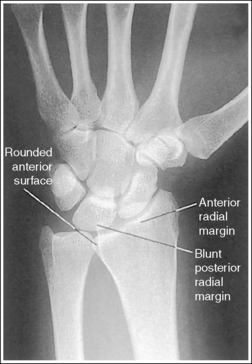

See Figure 4-29 and Box 4-11.

The wrist is positioned in a PA projection. The radial and ulnar styloids are at the extreme lateral and medial edges, respectively, of each bone. The radioulnar articulation is open, and superimposition of the metacarpal bases is limited.

• Rotation of the wrist and forearm is controlled by the position of the hand, elbow, and humerus. A PA projection is accomplished by abducting the humerus until it is positioned parallel with the IR and the elbow is in a lateral projection. The hand is then pronated, placing the wrist in a PA projection (Figure 4-31).

• External and internal hand and wrist rotation also cause the radial styloid to rotate out of profile and closes the radioulnar articulation.

The distal radius is demonstrated without foreshortening. The anterior and posterior articulating margins of the radius are nearly superimposed.

• The distal radial carpal articular surface is concave and slants approximately 11 degrees from posterior to anterior. Because the forearm is positioned parallel with the IR for a PA wrist projection, the slant of the distal radius causes the posterior radial margin to project slightly (0.25 inch or 0.6 cm) distal to the anterior radial margin, obscuring the radiocarpal joints.

• Distal radius superimposition: A PA wrist projection that demonstrates an excessive amount of the radial articulating surface, or if open radioscaphoid and radiolunate joint spaces are desired, view the distal radioulnar articulation to determine the correcting movement. The posterior edge of this surface is blunt, whereas the anterior edge is rounded. Study the distal end of a radial skeletal bone to familiarize yourself better with this difference. If a PA wrist projection is obtained that demonstrates the posterior radial margin distal to the anterior margin, the proximal forearm was elevated higher than the distal forearm (see Images 31 and 33). It should also be noted that when the wrist is medially rotated, the posterior radial surface is superimposed over the ulna. If the anterior radial margin is demonstrated distal to the posterior margin, the proximal forearm was positioned lower than the distal forearm. To superimpose the distal radial margins and to demonstrate radioscaphoid and radiolunate joints as open spaces (see Image 32), the proximal aspect of the forearm should be positioned slightly lower (5 to 6 degrees from horizontal) than the distal forearm.

The wrist is a very complex joint, with numerous bony components and movement possibilities. In an attempt to simplify the effect that different upper extremity movements have on the bony components, the following summary is offered. The positions of the elbow and hand affect forearm and wrist rotation and can be identified by the positions of the ulnar and radial styloid, respectively. When the elbow is in a lateral projection (humeral epicondyles aligned perpendicularly to IR), the ulnar styloid is in profile. When the hand is in a PA projection, the radial styloid is in profile.